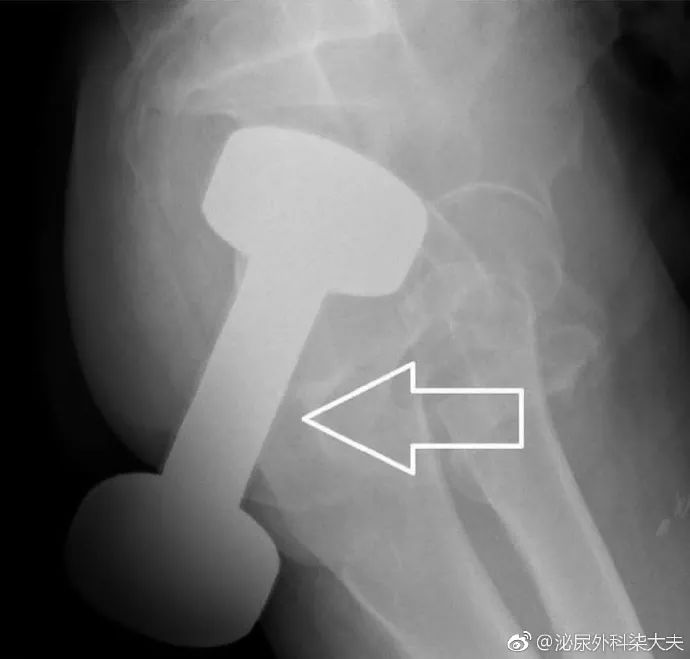

春节假临近结束,一位50多岁的男子发现了这种新奇玩法。

把哑铃塞进了肛门,到急诊后隐瞒了部分病史,直到拍片子的时候医生才发现了这个重达10斤的哑铃的“重大秘密”。

最后这个哑铃在足够的润滑和牵引后被从直肠中取出。